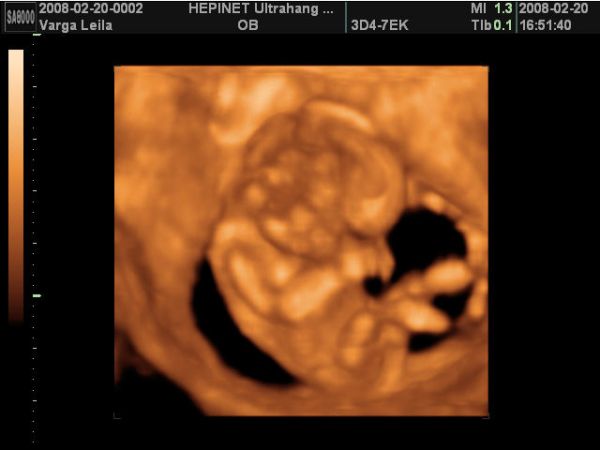

A babó a vizsgálat alatt végig tornázott, izgett-mozgott, úgy nevettem közben, mert annyira jó volt látni, hogy ficánkol, meg homorít a hátával.

Aztán a legvégén nagyon befúrta magát a méhfalba, úgyhogy az arcát nem tudtuk jobban megnézni.